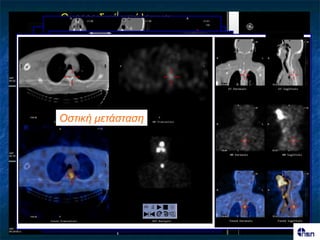

Οζηηθή κεηάζηαζε κεηάζηαζε

Θσρεοεηδηθό σπόιεηκκα; Θσρεοεηδηθό σπόιεηκκα Τπερθιείδηος ιεκθαδέλας Οζηηθή κεηάζηαζε κεηάζηαζε Λεκθαδεληθή